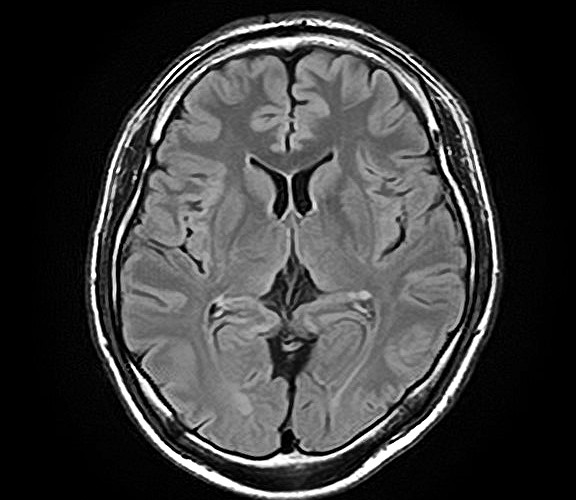

脳MRI・MRA検査

MRI(磁気共鳴画像)とMRA(磁気共鳴血管画像)を用いて、脳の断面や血管の状態を詳しく確認する検査です。

痛みや放射線被ばくの心配がなく、寝ているだけで脳の健康状態を調べることができます。

自覚症状のない小さな病変の早期発見を目指します。

この検査でわかること

• 脳出血の原因となる血管の異常

• 脳腫瘍の有無

• 加齢や認知症に伴う脳の変化

• 自覚症状のない小さな脳梗塞の跡